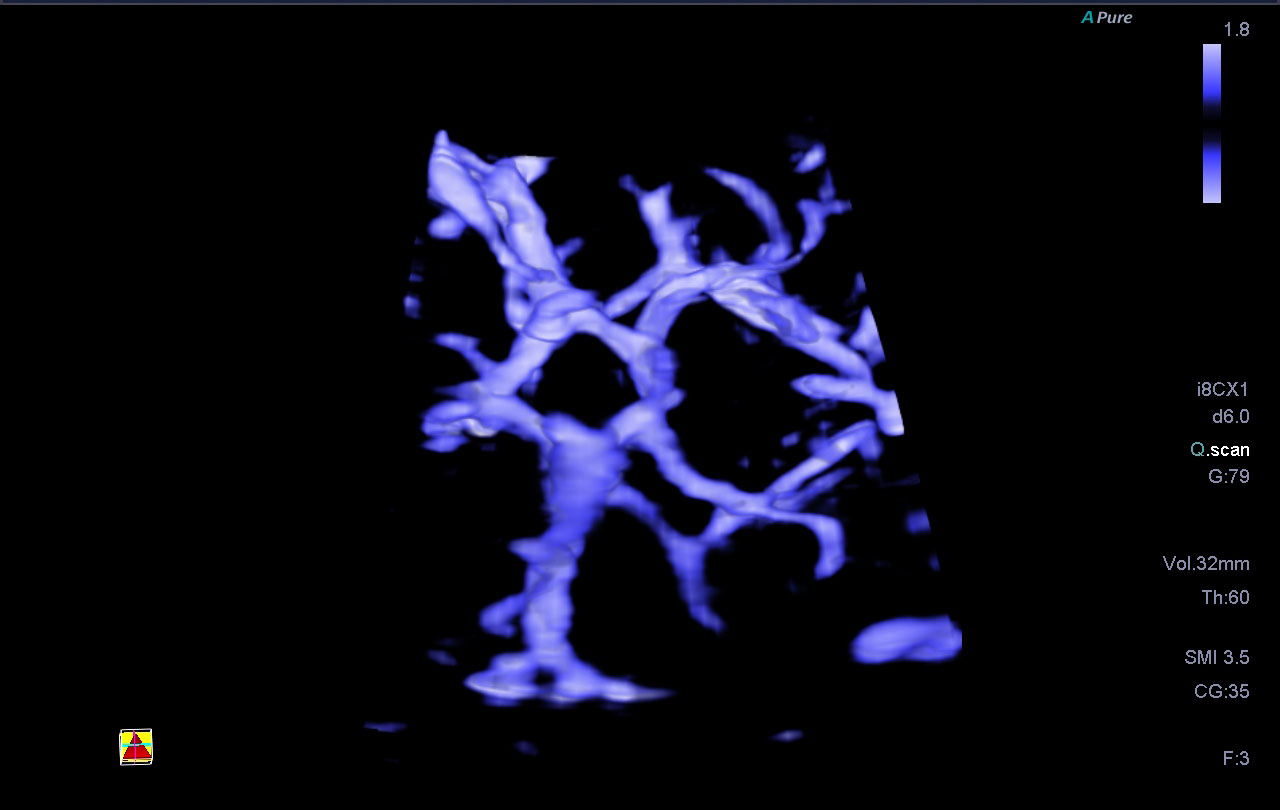

- Технология SMI для визуализации микроциркуляторного русла и отображения низкоскоростного кровотока в микрососудах

Smart 3D - это простой способ добавить объемную визуализацию к выпуклым и линейным преобразователям Aplio, поддерживая все режимы, включая SMI или изображения со сдвиговой волной

Технология Smart Sensor 3D создана для получения точных 3D-изображений. Линейный или конвексный датчики позволяют определять позицию объекта, рассчитать его объем, расстояние и угол, в том числе в режиме SMI

Технология Superb Micro-vascular Imaging в сочетании с высокой частотой кадров повышает диагностическую достоверность при оценке микроциркуляторного русла за счет отображения низкоскоростного кровотока в микрососудах. Кроме того, данная технология незамен